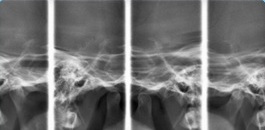

Visualização de forma planográfica das ATMs, com boca aberta e fechada.